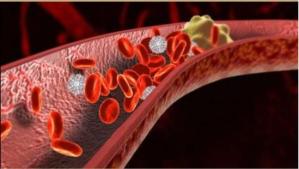

二、分解血管垃圾

地龍蛋白富含纖維蛋白溶解酶,能溶解新鮮及陳舊性血管垃圾,而且不影響體內的凝血機制,沒有引起出血的副作用。哪裏有障礙,它就疏通哪裏。活性地龍蛋白對老化的血管壁進行修修補補,恢復血管的光滑以及彈性。

四、降低血粘

使用地龍蛋白後,隨著血管的軟化、微循環的改善,降低了血液粘稠度,使異常的血液指標恢復正常,使微循環檢測由異常轉為正常,從而消除了發生心腦血管意外的隱患。